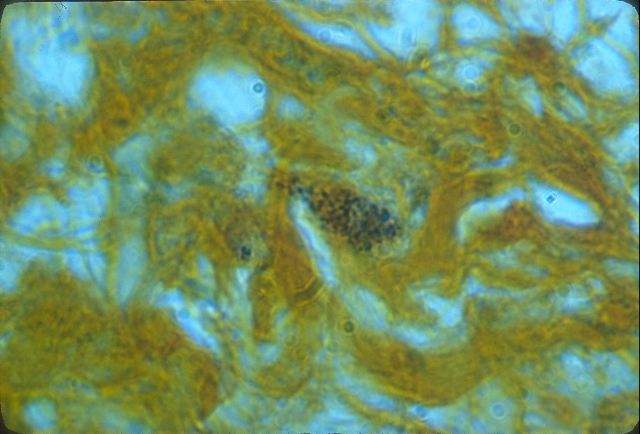

Figure 7. Mycosis fungoides (cutaneous T-cell lymphoma) of the skin. Arrows point to extracellular scattered coccoid forms in the deep dermis. Fite-Faraco (acid-fast) stain, x1000, in oil. Insert shows Staphylococcus epidermidis cultured from the lesion. Note the similar size and shape of the cocci cultured to the coccoid forms seen in vivo in the skin lymphoma. Ziehl-Neelsen (acid-fast) stain, x1000, in oil.